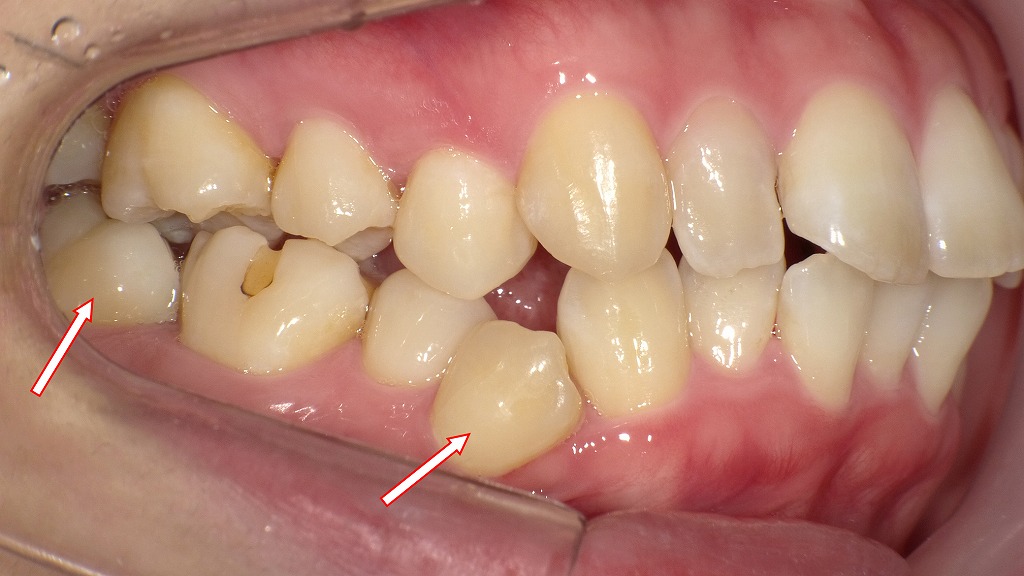

- 1.5. 同症例の臼歯部叢生の口腔内写真

- 1.5.1. 🦷 全体の所見

- 1.5.1.1. 右下第1小臼歯(右下4番)

- 1.5.1.2. 咬合関係(上下の噛み合わせ)

- 1.5.1.3. 食片圧入の懸念

- 1.5.2. 🔍 問題点まとめ

- 1.5.3. 🩺 臨床的考察